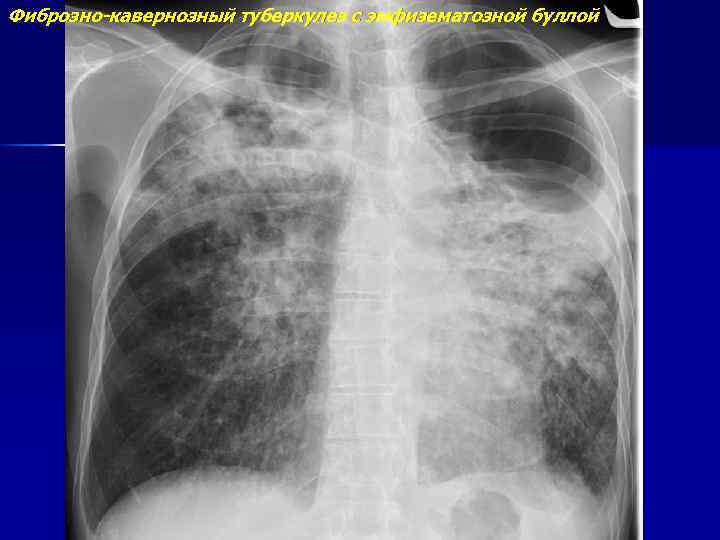

Симптомы и лечение инфильтративного туберкулеза легких

Раздел: Снимки-откровения